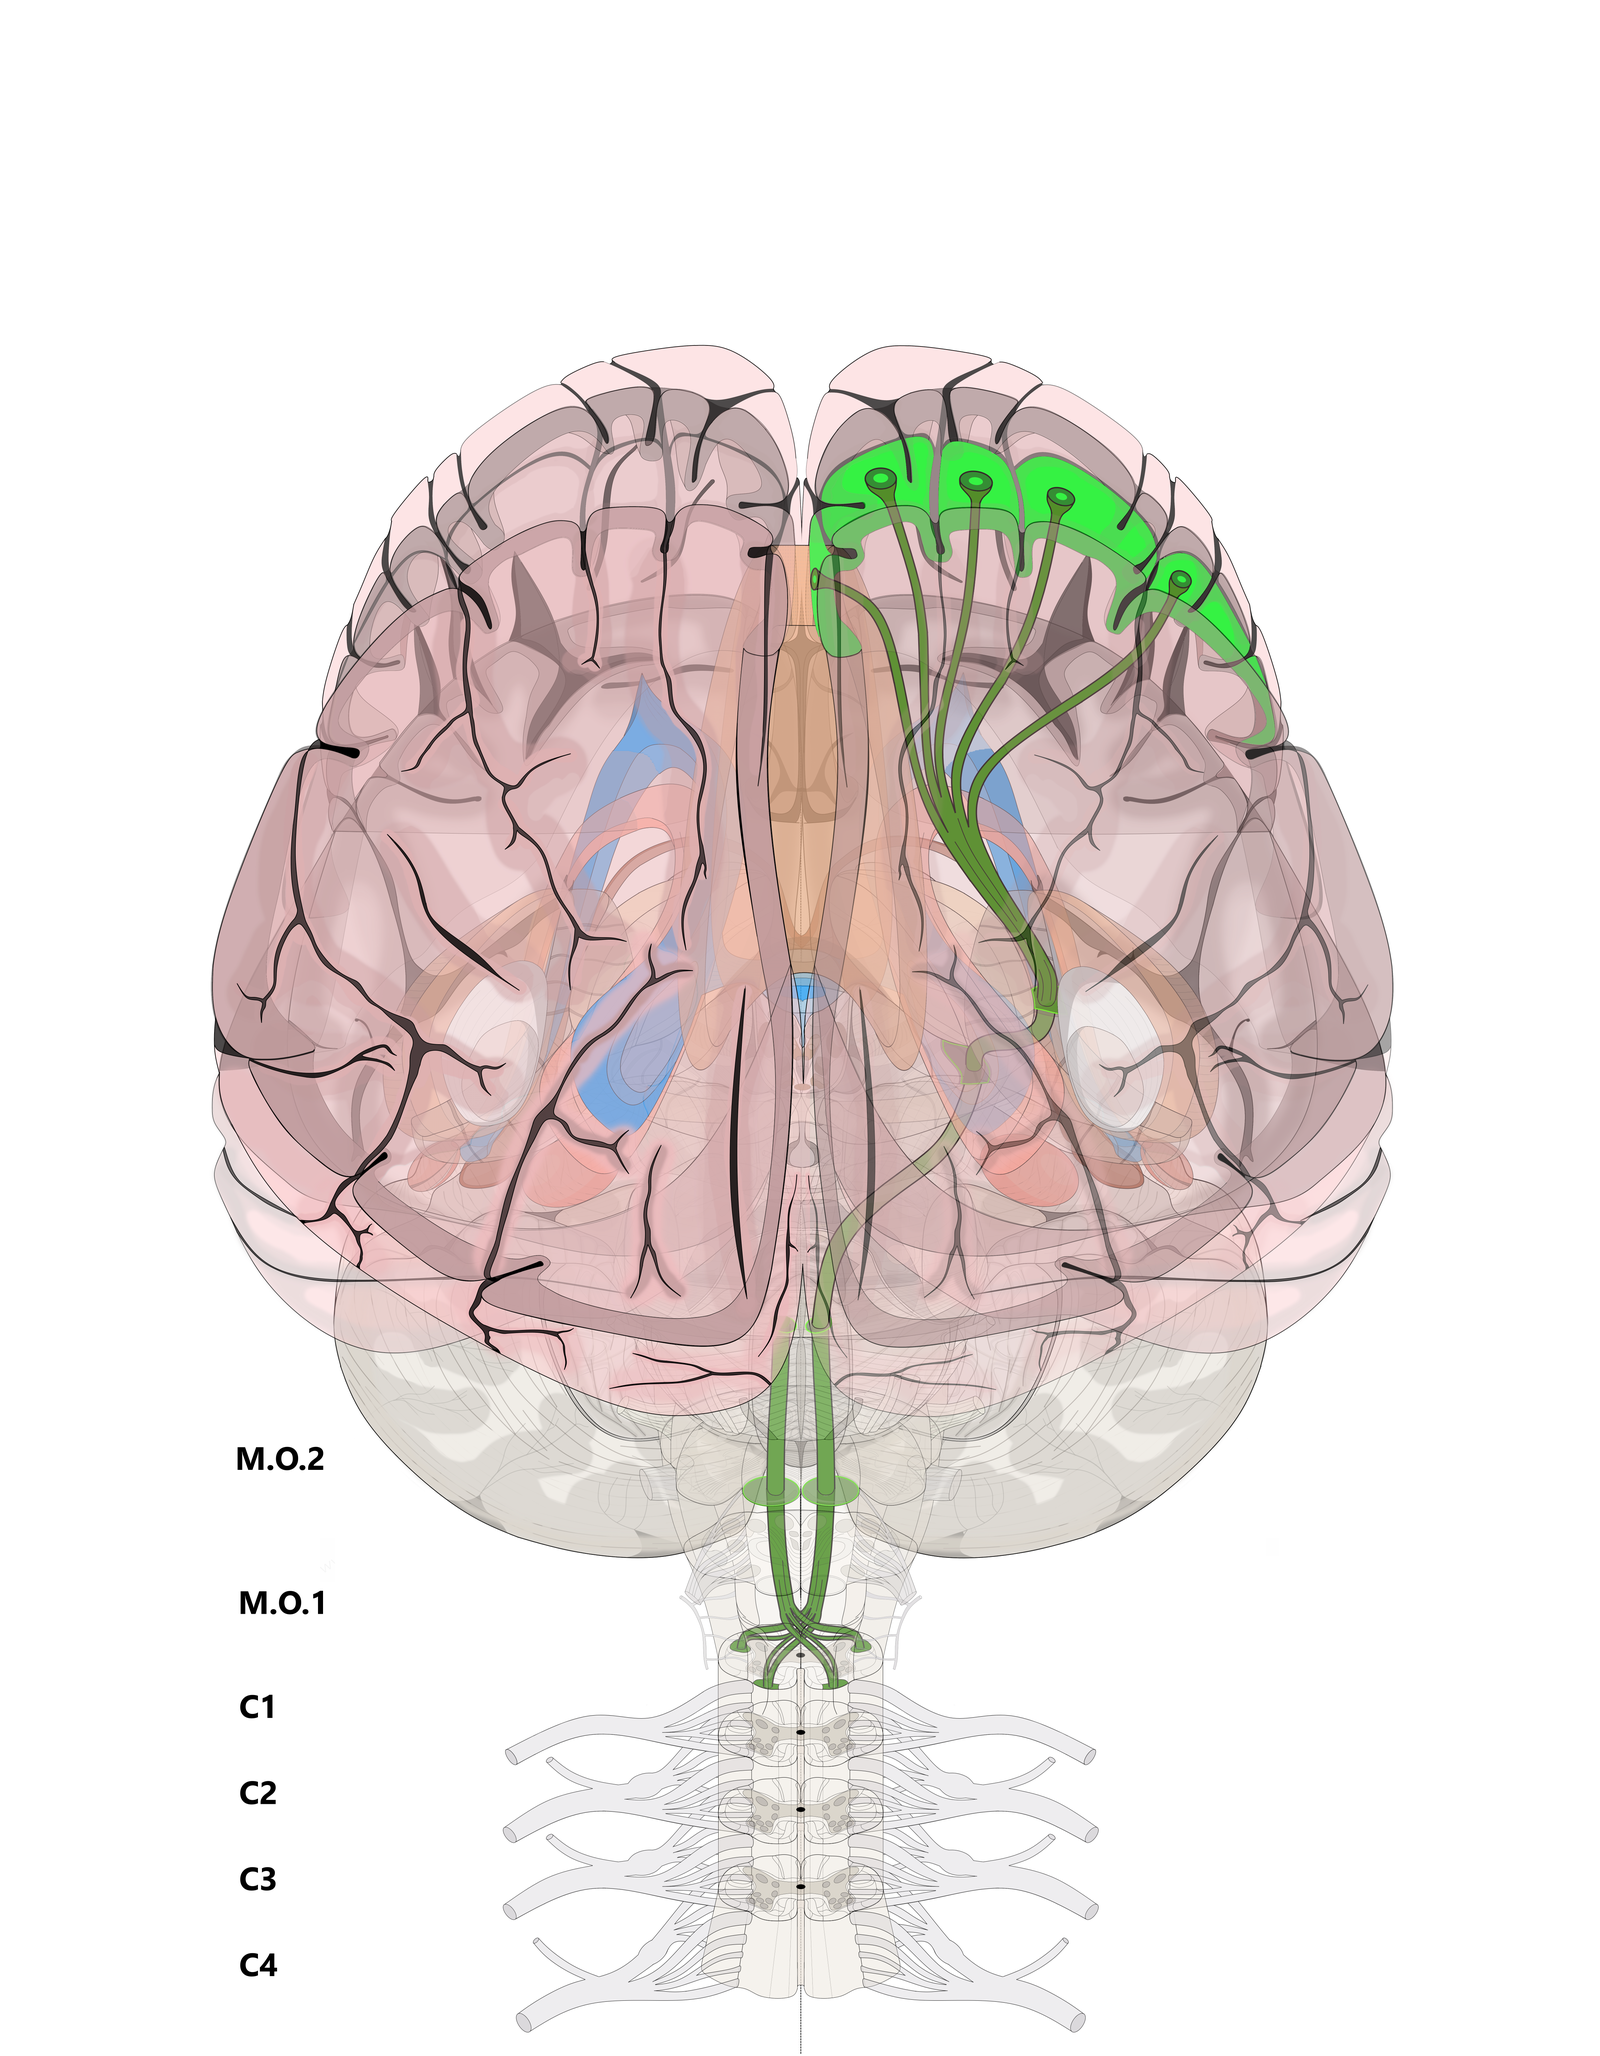

Пирамидная симптоматика в неврологии: ключевые аспекты